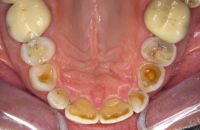

Voor de behandeling

Gebitsslijtage voornamelijk door knarsen. Aan de binnenkant zijn de tanden erg dun geworden en daardoor ook afgebroken. Door de diepe beet zijn de kiezen in onderkaak helemaal afgebroken.